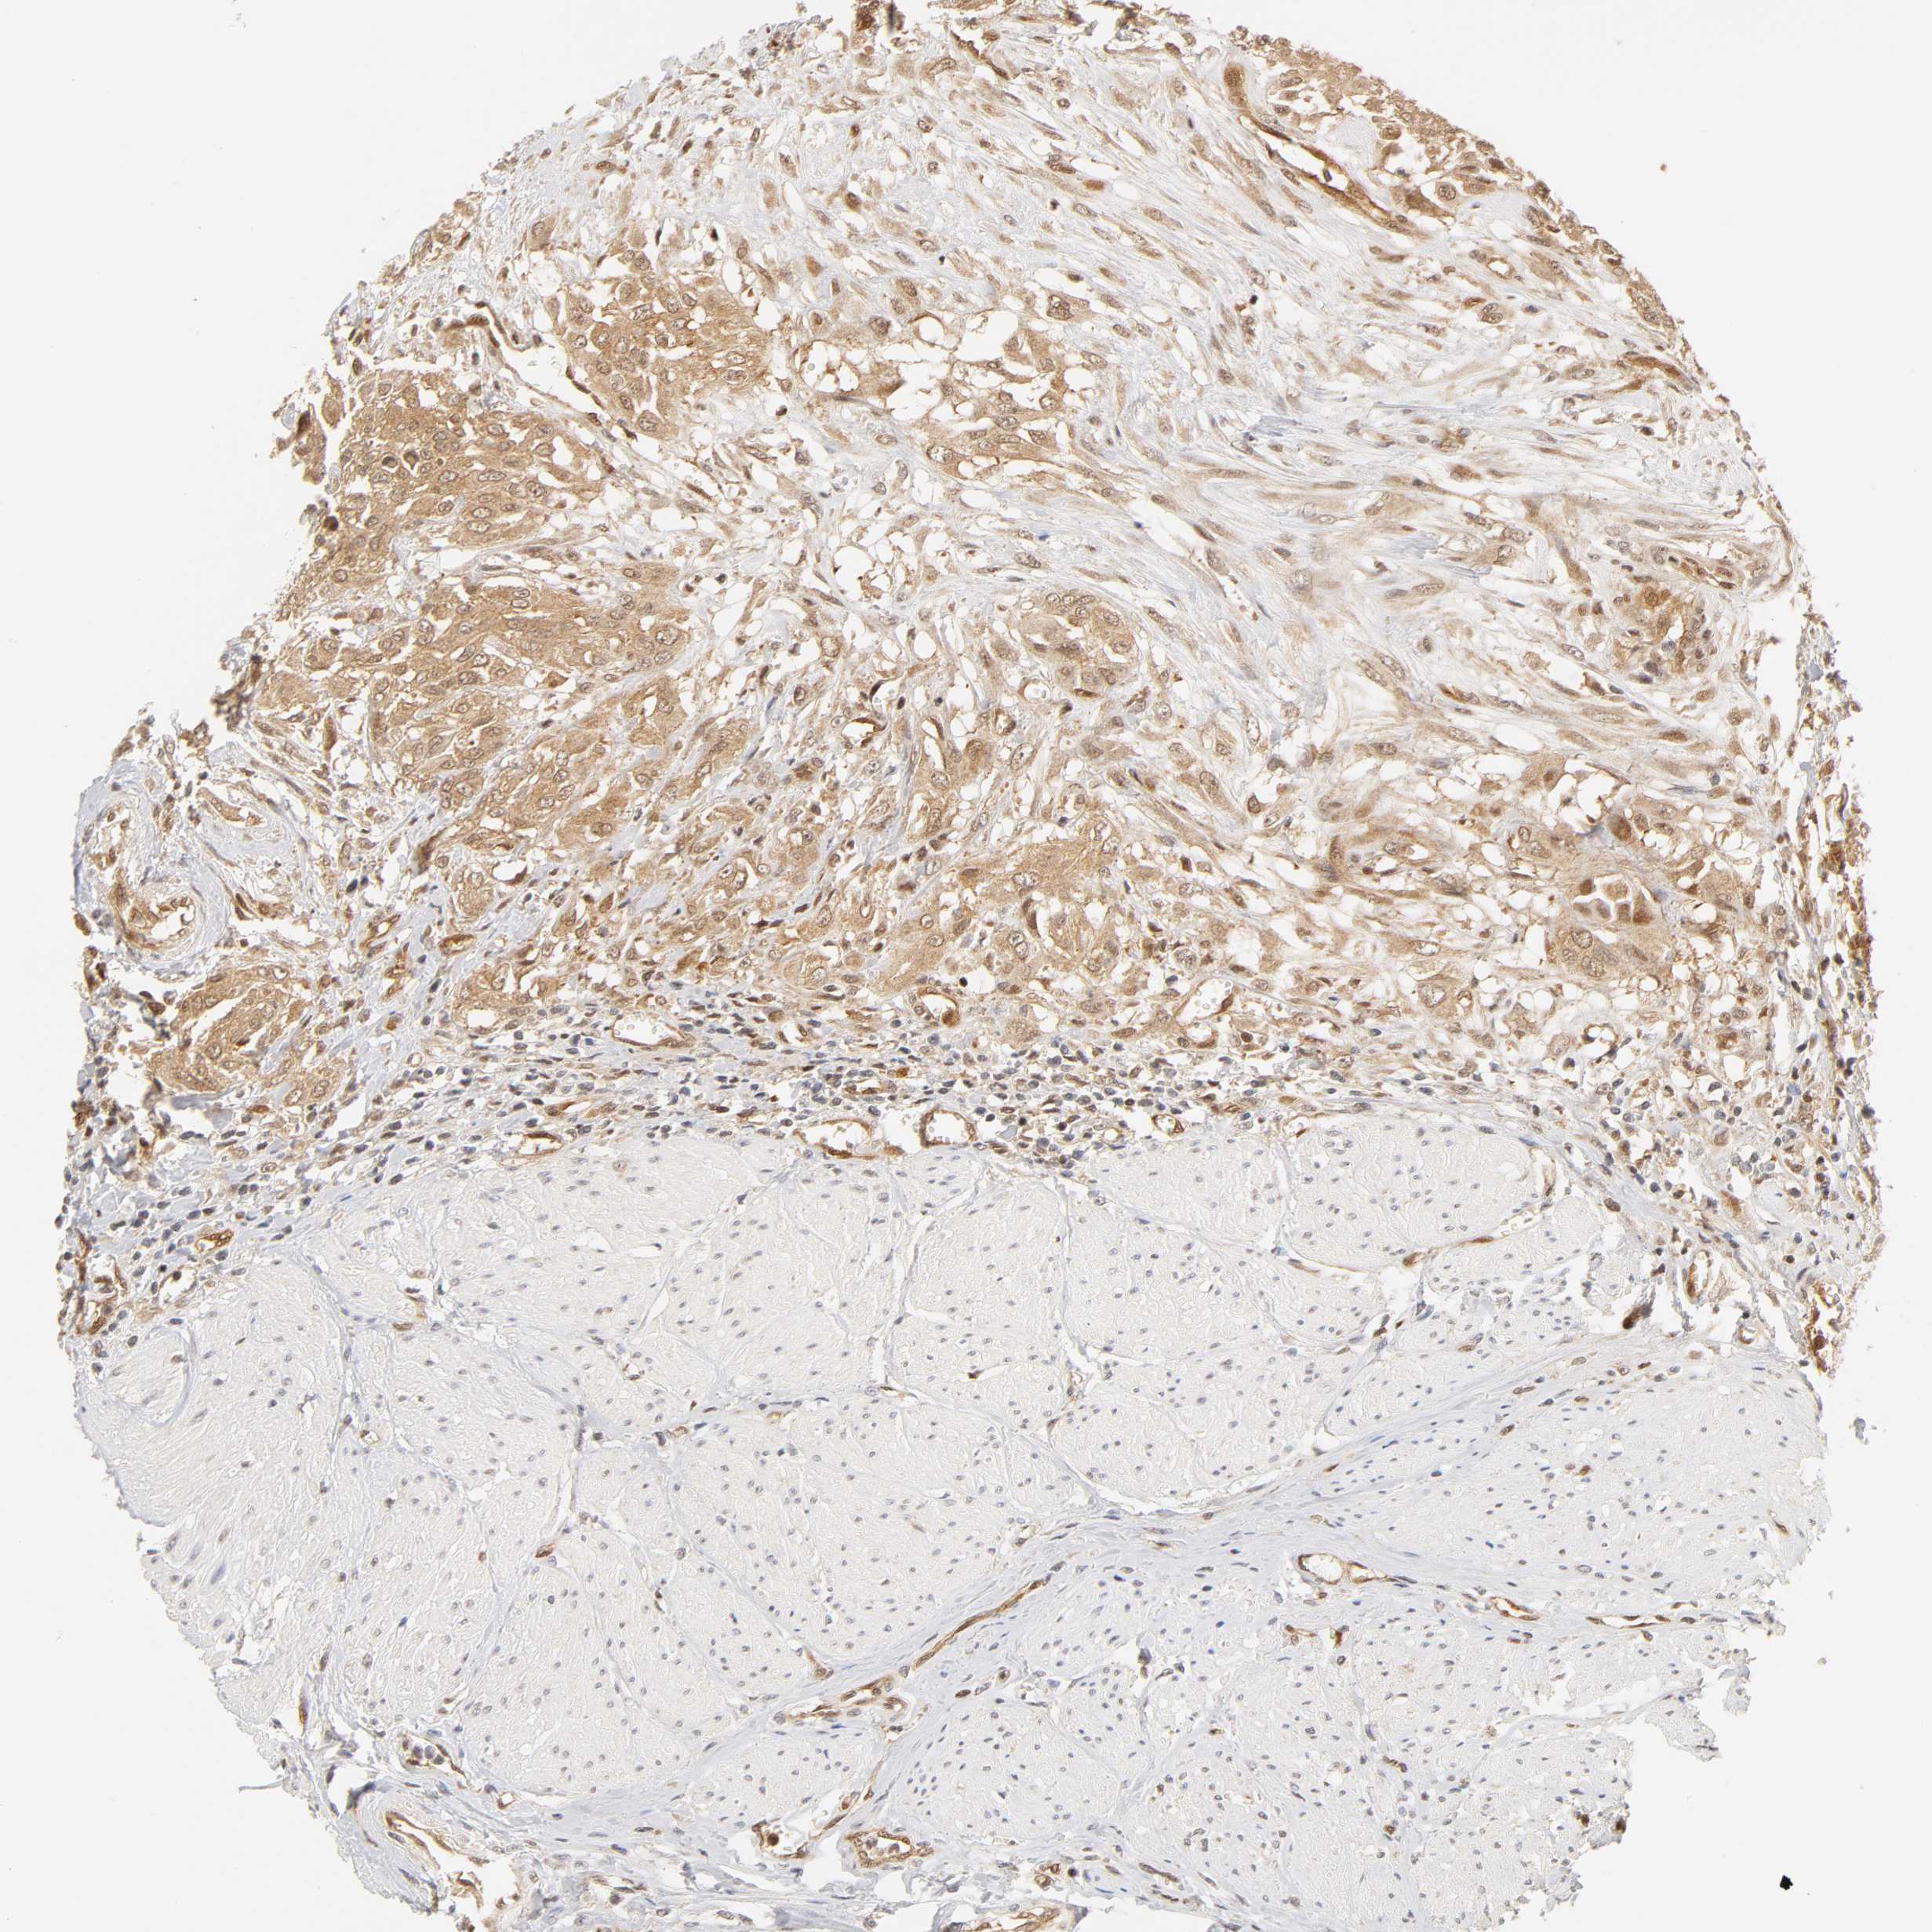

UROTHELIAL CANCER - Protein expressioni

A mouse-over function shows sample information and annotation data. Click on an image to view it in a full screen mode. Samples can be filtered based on level of antibody staining by selecting one or several of the following categories: high, medium, low and not detected. The assay and annotation is described here.

Note that samples used for immunohistochemistry by the Human Protein Atlas do not correspond to samples in the TCGA dataset.

Antibody stainingi

Antibody staining in the annotated cell types in the current human tissue is reported as not detected, low, medium, or high, based on conventional immunohistochemistry profiling in selected tissues. This score is based on the combination of the staining intensity and fraction of stained cells.

Each image is clickable and will lead to virtual microscopy that enables deeper exploration of all samples and also displays staining intensity scores, fraction scores and subcellular localization as well as patient and tissue information for each sample.

Antibody HPA003928

Antibody CAB004214

Staining

High

Medium

Low

Not detected

Intensity

Strong

Moderate

Weak

Negative

Quantity

>75%

75%-25%

<25%

None

Location

Nuclear

Cytoplasmic/membranous

Cytoplasmic/membranous,nuclear

Urothelial carcinoma, High grade

Urothelial carcinoma, Low grade